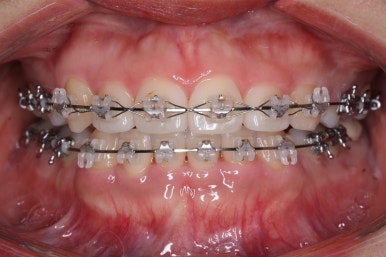

입 속 좌우 모습인데요. 문제점은 다음과 같이 있었어요.

윗니와 아랫니의 교합이 톱니바퀴처럼 맞물리지 않고 1대1 정면으로 맞닿고 있었습니다.

앞니쪽도 보면 윗니와 아랫니의 앞뒤 간격이 크게 차이나는 것을 볼 수 있습니다.

점점 개선이 되고 있는 모습이 보입니다.

정면으로 맞물렸던 교합도 좋아지고 있으며 이로 인해 자연스레 위아래의 앞뒤 간격도 맞닿게 되고 좁아지고 있습니다.

앞니, 어금니 맞물림이 좋아진 것을 볼 수 있습니다.